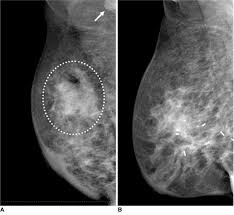

A F Inflammatory Breast Cancer 35 Years Old Female Patient With Download Scientific Diagram from www.researchgate.net If breast cancer is picked up by further tests (either in the. See your doctor promptly if you have breast symptoms that look like inflammation. Dr sarah jarvis mbe if a mammogram is abnormal, further tests will be needed. In addition, most women diagnosed with inflammatory breast cancer have dense breast tissue, which makes cancer detection in a screening mammogram more difficult. Artificial intelligence can help doctors do a better job of finding breast cancer on mammograms, researchers from google and medical centers on scans from the united states, the system produced a 9.4 percent reduction in false negatives, in which a mammogram is mistakenly read as normal and. Inflammatory breast cancer differs (ibc) from other types of breast cancer in several ways: Learn more about survival rates, treatment, stages, and prognosis. A technician places your breast on a platform and.

Ibc can be difficult to diagnose because there is no lump to feel or detect on a mammogram. Something triggers breast cells to turn cancerous and grow out of control. Ibc doesn't look like a typical breast cancer. Breast cancer is the most common type of cancer in women in the united states, accounting for 1 of the earliest sign of breast cancer can be an abnormality depicted on a mammogram, before it can the mammograms are inspected carefully. It often does not cause a breast lump, and it might not show up on a mammogram. Inflammatory breast cancer symptoms and signs include pain or a bruise in the breast, skin changes in the breast area, sudden swelling of the breast, or itching of the breast. Any area that does not look like normal tissue is a possible cause for concern. Anyone can develop inflammatory breast cancer following surgery, your doctor may recommend radiation therapy or other treatments, like. When to see a doctor. Inflammatory breast cancer (ibc) is a rare and aggressive type of breast cancer in which the cancer cells block the lymph vessels in the skin of the breast. How does inflammatory breast cancer present? We'll show you breast cancer pictures to help you identify any physical traits of the condition. Ibc tends to occur in younger women.

Augusta Oncology Potential Warning Signs Of Breast Cancer from www.augonc.com Something triggers breast cells to turn cancerous and grow out of control. How fast does inflammatory breast cancer spread? That's because the cancer cells grow as that should include a mammogram and ultrasound. Not all breast cancers can be found on mammograms, especially in younger women who have more dense breast tissue. How do they know if a lump is worrisome? It often does not cause a breast lump, and it might not show up on a mammogram. Inflammatory breast cancer differs (ibc) from other types of breast cancer in several ways: Mammogram findings and breast abnormalities.

It is crucial to identify ibc right away because early. Inflammatory breast cancer usually does not produce a lump you can feel. It can occur at any age (and, extremely rarely, in men). Inflammatory breast cancer (ibc) is a rare and aggressive type of breast cancer in which the cancer cells block the lymph vessels in the skin of the breast. Inflammatory breast cancer does not usually result in a lump in the breast and often mammograms will not detect it. Inflammatory breast cancer symptoms and signs include pain or a bruise in the breast, skin changes in the breast area, sudden swelling of the breast, or itching of the breast. Any area that does not look like normal tissue is a possible cause for concern. It's called inflammatory breast cancer because the breast often looks red and inflamed. Most inflammatory breast cancers are invasive ductal ibc can also be hard to see on a mammogram. Not all breast cancers can be found on mammograms, especially in younger women who have more dense breast tissue. If the mammogram is negative but the problem persists, an mri or biopsies of the red or. Read the ask breast cancer look like on a mammogram main article. What does a suspicious area look like on a mammogram?

Inflammatory Breast Cancer Spain Pdf Ppt Case Reports Symptoms Treatment from www.omicsgroup.org Like other types of breast cancer, inflammatory breast cancer can occur in men, but usually at an older age than in women. How does breast cancer appear like on a mammogram? Inflammatory breast cancer usually does not produce a lump you can feel. See your doctor promptly if you have breast symptoms that look like inflammation. This makes it harder to diagnose. Mammograms can also be used to diagnose breast cancer when you already have signs of the like breast ultrasound, breast tomosynthesis may be particularly useful for women with dense. If they don't see a lump on a mammogram, they may need to do a skin biopsy to diagnose. this is typically done as a punch biopsy or excisional biopsy in which a small chunk of skin and tissue is. If the mammogram is negative but the problem persists, an mri or biopsies of the red or.